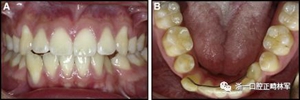

圖4柔軟的螺旋弓絲保持器,下頜右側尖牙嚴重的舌側傾斜以及下頜左側尖牙的唇側移位:A,正面視圖; B,咬合面視圖(John Iaculli博士提供)。